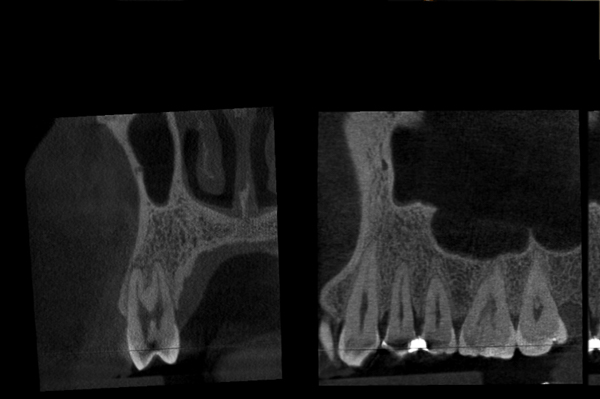

Il caso presenta la riabilitazione di un premolare superiore interessato dal fallimento di un trattamento endodontico in una paziente donna di 37 anni, non fumatrice e con una buona igiene.

A seguito dell'analisi radiografica viene pianificata l'estrazione atraumatica del premolare con l'inserimento contestuale di un impianto Shelta. La riabilitazione immediata viene eseguita con un pilastro XA per protesi avvitata, su cui viene fissato un provvisorio realizzato in laboratorio secondo i principi dei profili di emergenza della tecnica B.O.P.T.

Donna, 37 anni, non fumatrice, con una buona igiene, si presenta in studio con un fallimento del trattamento endodontico dell'elemento 1.4.